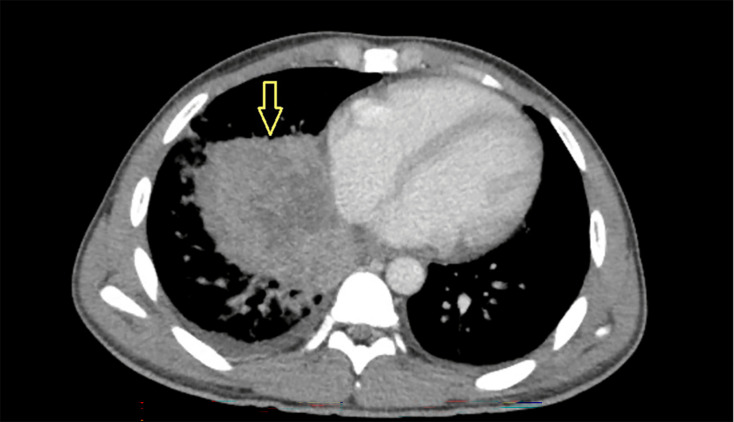

Introduction. Coccidioidomycosis, or Valley fever, is a fungal disease caused by Coccidioides species, prevalent in parts of the southwestern United States. It usually results from inhaling spores from soil and is a common cause of pneumonia in these regions. Case Presentation. We present a unique case of coccidioidomycosis in an immunodeficient male patient secondary to human immunodeficiency virus infection with poor adherence to anti-retroviral treatment. After presenting with non-specific symptoms and pre-syncope, he was initially diagnosed with pneumonia based on chest X-ray findings, but his symptoms failed to improve with antibiotics. He was treated for presumed pulmonary histoplasmosis following a positive histoplasma urine antigen test. However, the patient worsened clinically. Following a computed tomography scan demonstrating a large necrotic lung consolidation, fungal stain and culture of tissue biopsied through endobronchial ultrasound confirmed coccidioidomycosis. The patient received 2 weeks of liposomal amphotericin with clinical improvement before discharge with itraconazole. Conclusion. The histoplasma antigen test can be falsely positive due to cross-reaction with other fungal infections like blastomycosis, paracoccidioidomycosis or talaromycosis, and less frequently, coccidioidomycosis or aspergillosis. Diagnosis of coccidioidomycosis requires a high index of suspicion outside the expected geographic distribution in the appropriate clinical setting. Our case highlights the risk of false-positive antigen test results and the importance of invasive diagnostics, including bronchoscopy to obtain fungal cultures, if the diagnosis remains uncertain.